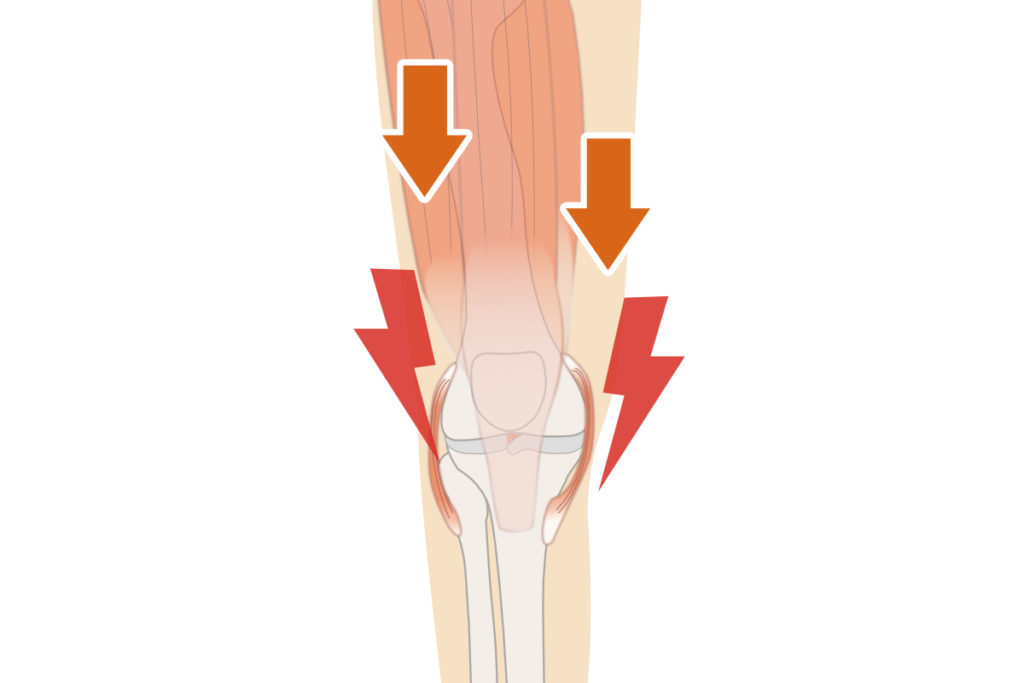

- 膝周辺の筋肉への負担

「膝の骨の変形」は痛みに対する1つの原因になりますが、実際には

”骨の変形により、筋肉や靭帯に負担が大きくなり痛みを感じている”

ようなケースも。

膝の痛みは筋肉や靭帯への

負担が大きくなることで発生

骨が変形すると……

▼

筋肉・靭帯の負担が増えるため

膝の痛みが出やすい